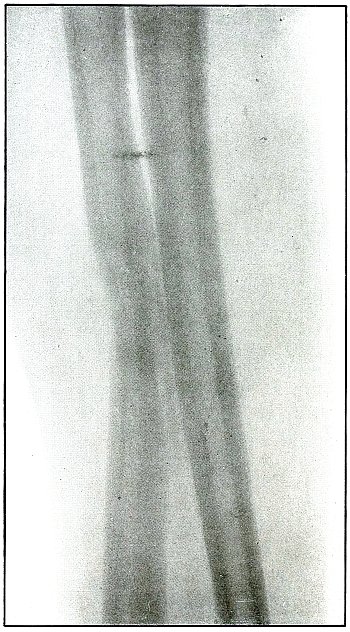

Gunshot fracture, radius and ulna |

52 |

| 22. |

Gunshot fracture, radius and ulna |

54 |

| 23. |

Gunshot fracture, radius and ulna |

56 |